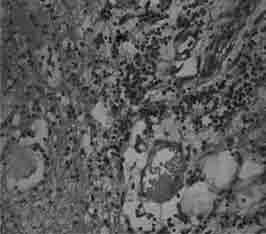

Язвенная болезнь относится к наиболее распространенным заболеваниям органов пищеварения. Врачи первого контакта (терапевты, общей врачебной практики) часто прибегают к стандартной диагностической и лечебной тактике при ведении данной категории пациентов. Однако определенная часть пациентов имеет сопутствующую патологию, нередко являющуюся фоном, отягощающим течение основного заболевания, и требует диффенцированного подхода к терапии с учетом фоновой патологии. Отмечены особенности морфологических изменений желудка у пациентов с дисплазией соединительной ткани, особенности моторно-эвакуаторной функции желудка и двенадцатиперстной кишки. По материалам собственных исследований сделаны выводы, позволяющие оптимизировать лечение язвенной болезни. В монографии показана целесообразность скрининга гастродуоденальных заболеваний при наличии внешних проявлений соединительнотканной дисплазии, в значительной мере это касается пациентов молодого возраста, имеющих симптомы диспепсии. Предложен комплекс мероприятий, направленных на коррекцию стандартизированного подхода к терапии язвенной болезни.